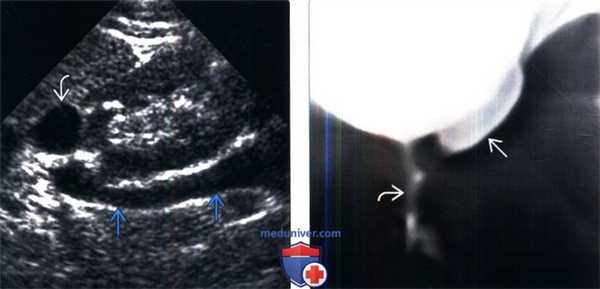

(Левый) На продольном УЗ срезе визуализируется две почечные лоханки, разделенные почечной паренхимой.

(Правый) На продольном УЗ срезе визуализируются выходящий из почки раздвоенный мочеточник. Гидронефроз в верхней половине почки, в нижней половине также наблюдается небольшое расширение, связанное с пузырно-мочеточниковым рефлюксом.